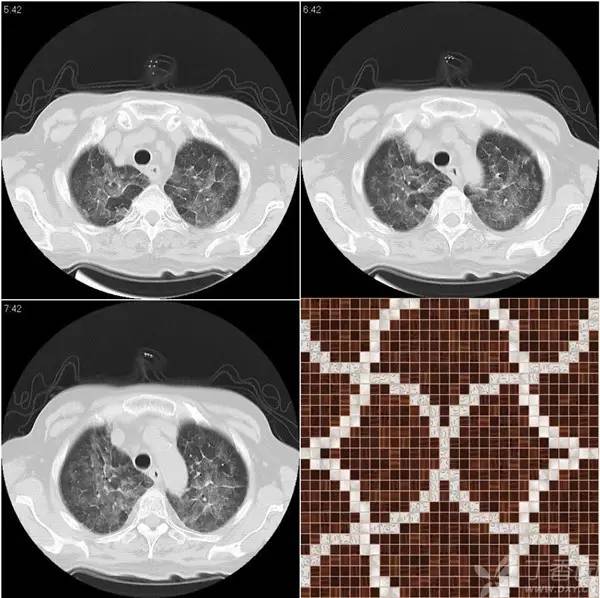

马赛克征表现为肺密度增高区和肺密度减低区夹杂相间呈不规则的补丁状或地图状。吸气相上的马赛克征可能是由浸润性肺疾病、空气潴留或血管阻塞引起。呼气相的马赛克征更加明显,则可确定有空气潴留引起。

血流分配到那些正常肺组织区的密度则增高,表现为相应肺密度区域的增高。这种异常的低密度和正常肺组织的相对高密度结合起来,就形成了所谓的「马赛克分布」。

这种征象的形成主要有小气道疾病、血管性疾病如肺栓塞、浸润性肺病如卡氏非囊虫肺炎、慢性嗜酸性肺炎、过敏性肺炎及化脓性肺炎等。